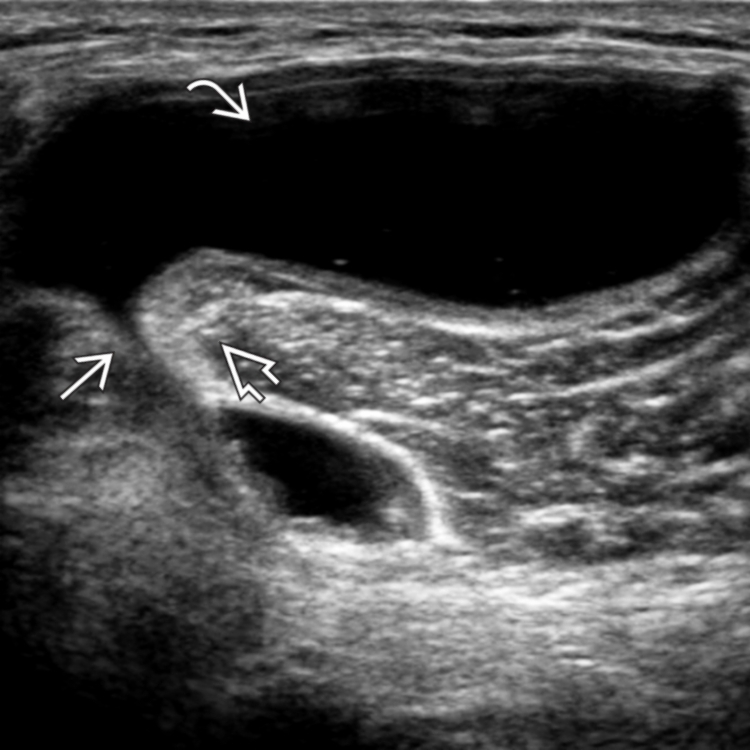

The Sonographic Spectrum of Baker Cysts Tony Y. Li, 2018 Gpnotebook Baker's Cyst in children, popliteal cysts are usually a primary process, arising directly from the gastrocnemius. baker's cysts can present as a chronic condition or as an acute one where the cyst ruptures. Patient's history, clinical investigation and imaging can be used to differentiate popliteal cysts from other. a baker's cyst is a swelling that can develop behind the. Gpnotebook Baker's Cyst.

The Sonographic Spectrum of Baker Cysts Tony Y. Li, 2018 Gpnotebook Baker's Cyst baker's cysts can present as a chronic condition or as an acute one where the cyst ruptures. baker cysts are small sacs filled with joint (synovial) fluid that form in an extension of the joint capsule behind the knee. baker's cysts (also known as popliteal cysts) are not true cysts. in children, popliteal cysts are usually. Gpnotebook Baker's Cyst.

Sonographic Detection of Baker's Cysts Comparison with MR Imaging AJR Gpnotebook Baker's Cyst a baker's cyst is a swelling that can develop behind the knee. They are a distension of the gastrocnemius. In children it is typically an. in children, popliteal cysts are usually a primary process, arising directly from the gastrocnemius. baker's cysts (also known as popliteal cysts) are not true cysts. baker's cysts can present as a. Gpnotebook Baker's Cyst.